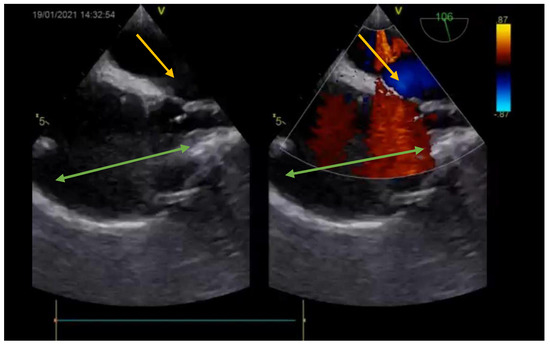

The diagnosis was based on the transthoracic echocardiography (Figure 1 and Figure 2). It revealed an SV-ASD with PAPVD which appeared to open in the right atrium, a dilated right atrium and ventricle, and a left-to-right shunt with Qp:Qs of 2.3 (Qp-pulmonary flow/Qs-systemic flow). The patient had normal pulmonary artery pressure, which was measured during echocardiography.

Figure 1. Preoperative echocardiography (bicaval view—Doppler; SVC—green arrow; right atrium—orange arrow; interatrial septum—white arrow) showing the ASD (yellow arrow).